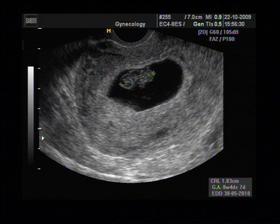

8/10 jsme se byli podívat u paní doktorky, zda testy nelhaly - a ono n e. Puclík měřil 0,37cm a co je důležité - srdíčko už funguje. Táta s Pepínem byli v ordinaci s námi, a když se na monitoru objevilo mimi, tak ho Pepíno pozdravil - udělal mu "ahoj" 🙂 oba nás to s Honzou dojalo. Další kontrola 22/10.